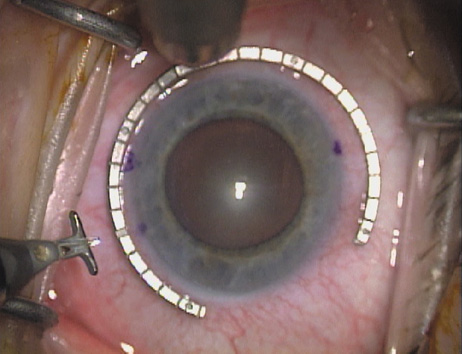

Case 2 is a 79-year-old woman who presented with a very dense left cataract. Her refraction was recorded at −2.25 +2.75 × 125 with a difficult end point. Her manual keratometry and topography measurements were consistent and revealed slightly less than 1.75 D at 120 degrees. Because of the questionable refraction, greater value was placed on the corneal measurements. Based upon the cataract nomogram, the plan was for paired LRIs of 40 degrees to be placed over the steep 120-degree axis (Figs. 1219).

Fig. 12. In this left eye, the steep meridian is at the 120-degree axis and has been delineated by opposing limbal marks. The upper left hand ink mark represents the 6:00 position for orientation. (Reprinted from Hardten DR, Lindstrom RL, Davis EA. Phakic Intraocular Lenses: Principles and Practice. Thorofare, NJ: SLACK Incorporated, 2004, with permission.)